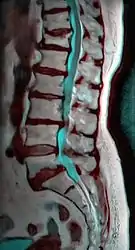

MRI

Magnetic resonance imaging (MRI) is the preferred advanced imaging technique for evaluation of spondylolisthesis.[26] Preference is due to effectiveness, lack of radiation exposure, and ability to evaluate for soft tissue abnormalities and spinal canal involvement.[26][27] MRI is limited in its ability to evaluate fractures in great detail, compared to other advanced imaging modalities.[28]